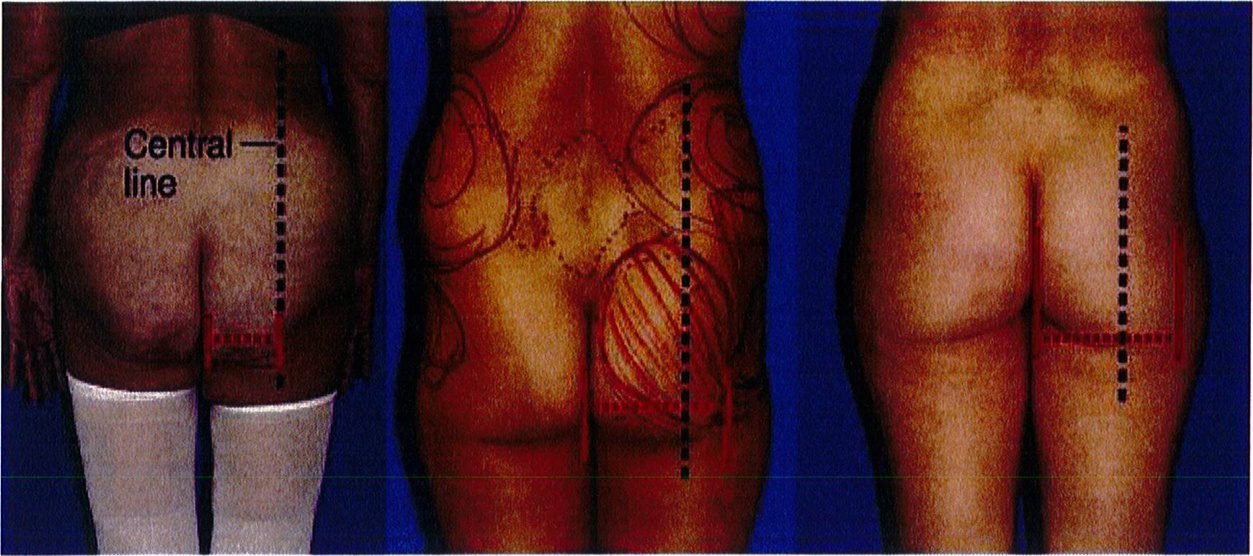

sẽ kêt luận đây là cơ mông có chiêu rộng hẹp. Nếu nó đi qua đường giữa mông này khoảng 10-30% thì được quy về chiều rộng bình thường. Và nếu vượt trên khoảng 40-50% thì được gọi là rộng. Mông đạt tiêu chuẩn thẩm mỹ ở người trẻ thuộc nhóm chiều rộng bình thường, và nếp lăn mông bên dưới chạy đến đường giữa hoặc chỉ vượt qua đường giữa mông đó 1 đoạn ngắn (Hình 1A).

Hãy tưởng tượng cơ mông nằm trên khung chậu với trục đối xứng là đường liên mông. Theo lý thuyết, cơ mông có khối lượng bằng nhau ở hai bên và có hình dạng của 1 quả bóng đá. Để đánh giá kỹ hơn, vẽ một đường nằm ngang (Hình 18). Điều này cho phép chia mông thành 4 góc phần tư: trên trong, trên ngoài, dưới trong và dưới ngoài. Vòng mông lý tưởng là vòng mông phân bố đểu tổ chức ở 4 vùng trên. Khi đánh giá từ góc nhìn sau trước, mỗi góc trong số 4 góc này phải được đánh giá xem chúng bằng nhau hay thiếu so với các góc còn lại như thế nào.

Để xác định chiều rộng của khối cơ, vẽ 1 đường thẳng ở giữa mông (song song với đường liên mông). Sau đó xác định chiều rộng của nền khối cơ mông lớn từ đường giữa của cơ thể. Nếu đường đo nền khối cơ này (như hình 13, ảnh thứ 2 từ trái sang) không vượt quá đường thẳng vừa vẽ, chúng ta

Narrow base (50% line) Normal base Wide base (10-30% beyond central line) (40-50% beyond central line)

Hình. 17. Cách xác định chiều rộng phần nền khối cơ mông: hẹp, trung bình/ bình thường, hoặc rộng.

Narrow base(50% line : Hẹp (50% đường giữa) Normal base(10-30% beyond central line): Trung bình (vượt đường giữa 10- 30%) Wide base (40-50% bevond central line): Rôna (vươt đường aiữg 40-50% )

Hình. 18. Hình ảnh 4 góc phần tư: 1: góc trên trong, 2: góc trên ngoài, 3: góc dưới trong, 4: góc dưới ngoài. Nên đánh giá đầy đủ từng góc một.

Gluteal Quadrants: Góc phần tư Mid-reference line: Đường tham chiếu ở giữa mông